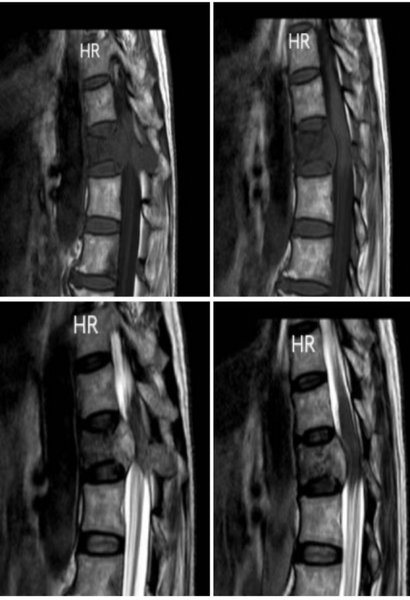

治疗前脊柱核磁共振

来自林甸县54岁的刘某某,因右侧乳腺癌术后5年腰痛半年,来齐医附属二院就诊,入院时病人双下肢活动欠佳,双足麻木伴有排尿困难尿潴留,入院后进行相关检查,见胸12椎体骨转移瘤,椎体破坏,脊髓受压,经乳腺外科主任闫卫刚专家团队周密分析及评估后,针对乳腺癌骨转移晚期病人,以全身化疗+骨保护治疗为主,但是考虑病人胸椎转移伴脊髓受压,病人随时可能出现截瘫的风险,单纯以化疗无法维持病人日常生活,经过与骨外三病区副主任刘艳南团队合作,制定手术+化疗的方式对病人先行“胸椎骨折球囊扩张成形术”以保持脊柱的稳定,再行全身化疗联合骨保护治疗。现病人已可以自行行走,排便排尿均已恢复正常。